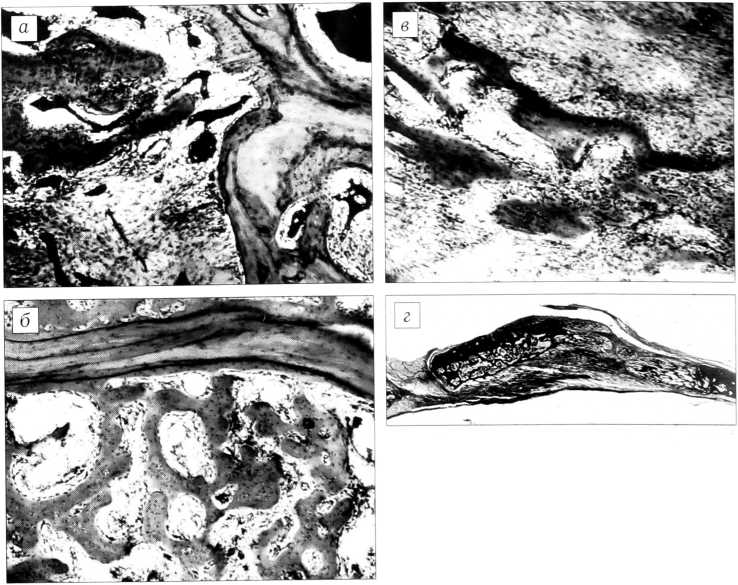

Рис. 1. Замещение дефекта костей свода черепа путем перемещения в нем фрагмента на питающей ножке. Темп дистракции 1 мм в сутки. а — 7-й день дистракции: костные трабекулы, растущие от края дефекта. Окраска гематоксилином и эозином. Об. 6,3, ок. 10; б — 14-й день дистракции. Окраска пикрофуксином по Ван-Гизону. Увеличение лупное; в — 14-й день дистракции: формирование костных трабекул на поверхности опила материнской кости. Окраска гематоксилином и эозином. Об. 6,3, ок. 10; г — 14-й день дистракции: формирование костных трабекул на основе коллагеновых волокон в апикальном отделе регенерата. Импрегнирование серебром. Об. 6,3, ок. 10; д — 21-й день дистракции. Импрегнирование серебром. Увеличение лупное.

На гистотопограммах в диастазе между фрагментом и каудальным краем дефекта, равном 5- 7 мм, определялась в основном скелетогенная ткань. Со стороны фрагмента и от края дефекта в диастаз на 0,5-1,1 мм врастали костные трабекулы (рис. 1, а), ориентированные по направлению перемещения фрагмента. В последнем значительная часть остеоцитов была лишена ядер, костный мозг по ходу спицевого канала некротизирован. Вокруг фрагмента обнаруживались рассасывающиеся костные опилки и мелкие осколки. Между передним краем дефекта и перемещаемым фрагментом содержались соединительная ткань и атрофичные мышечные волокна.

При микроскопическом исследовании выявлено заполнение диастаза костной и соединительной тканью (рис. 1, б—г). При этом протяженность костного отдела регенерата от заднего края дефекта и от перемещаемого фрагмента составляла 3-9 мм. В соединительной ткани, расположенной между костными отделами регенерата, коллагеновые волокна и сосуды микро- циркуляторного русла имели направление, совпадающее с вектором перемещения фрагмента. Вокруг капилляров отмечалось скопление малодифференцированных соединительнотканных клеток, в некоторых из них были видны фигуры митоза. Эта соединительнотканная прослойка («зона роста» регенерата) сливалась с соединительной тканью, заполнившей пространство между твердой мозговой оболочкой и фрагментом. Во фрагменте определялись инъецированные тушью капилляры, часть остеоцитов была лишена ядер, на дорсальной и вентральной поверхностях образовывался слой костного вещества толщиной 0,2— 0,4 мм. Краниальный конец фрагмента подвергался резорбции, по ходу спицевых каналов отмечалась эндостальная реакция. В толще соединительной ткани, образовавшейся за счет пролиферации клеток наружного слоя твердой мозговой оболочки и заполнившей область дефекта, наблюдались островки остеогенеза. Пространство между передним краем дефекта и краниальным концом перемещаемого фрагмента было заполнено богато васкуляризированной соединительной тканью.

При микроскопическом исследовании (рис. 1, д) отмечено заполнение диастаза костной и соединительной тканью. При этом костный отдел регенерата со стороны перемещаемого фрагмента по протяженности (6-7 мм) превышал регенерат, отходящий от материнского ложа (2,2-5,5 мм). Между костными отделами располагалась зона соединительной ткани, состоящая из продольно ориентированных коллагеновых волокон, капилляров и клеток фибробластического ряда. Соединительная ткань прослойки сливалась с твердой мозговой оболочкой, толщина которой в зоне дефекта достигала 0,2 мм.